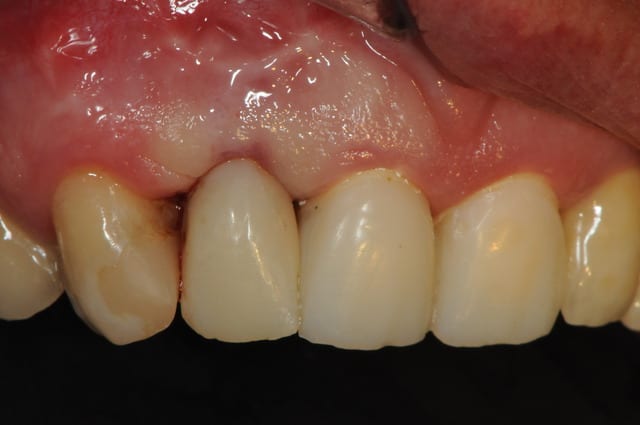

voici - voilà:

photo

1: j+ 2 ou 3 jours

2: j+8 mois

3-4-5: j+ 2 ans

sur la photo 3 on voit à la gencive que l'aspect est moins granité au niveau du col.

c'était ça l'indice pour trouver Charlie.